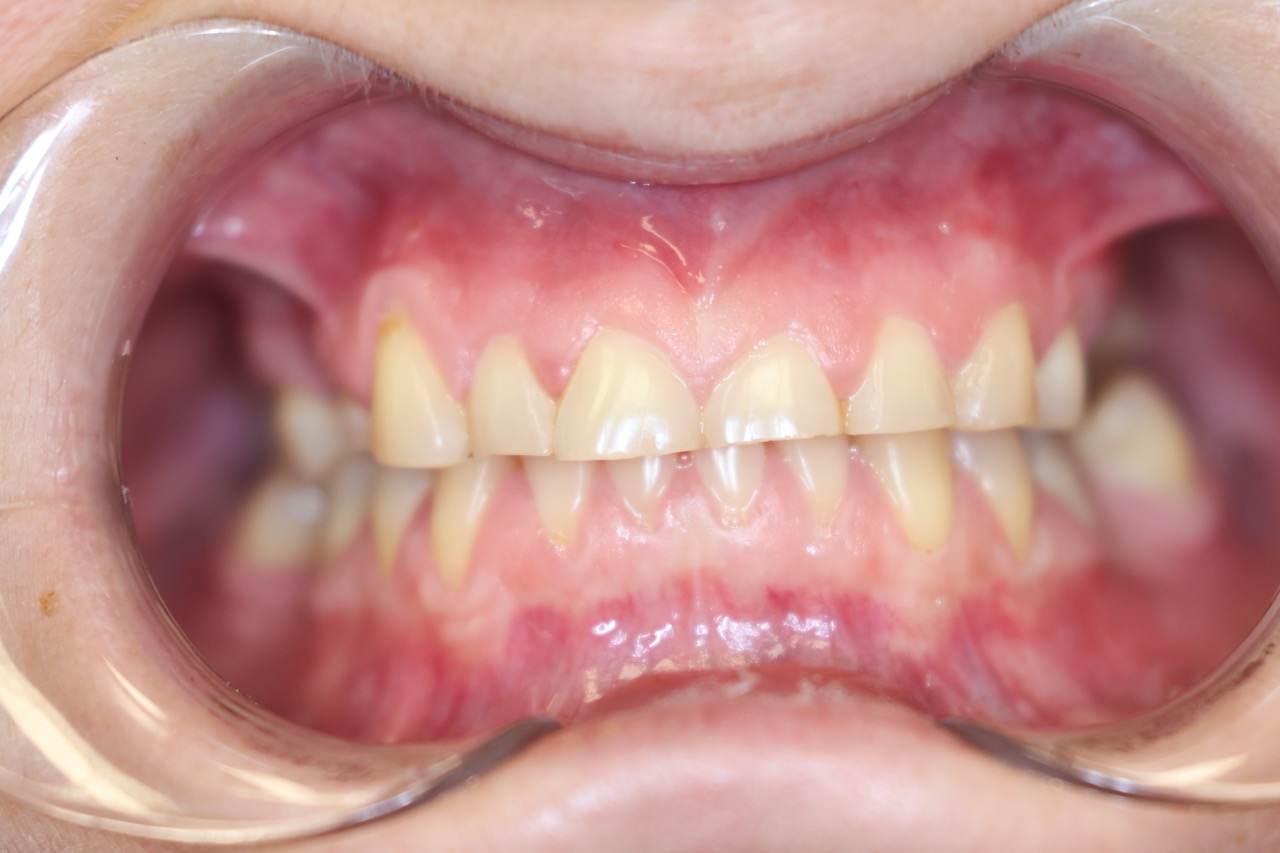

Bruksizm to nawykowe, niekontrolowane zaciskanie szczęk i zgrzytanie zębami, które najczęściej występuje podczas snu, ale może pojawiać się także w ciągu dnia. Jest to schorzenie o podłożu wieloczynnikowym, często związane ze stresem, wadami zgryzu, napięciem mięśniowym lub problemami neurologicznymi. Bruksizm prowadzi do nadmiernego ścierania szkliwa, uszkodzeń zębów, bólu szczęki oraz bólów głowy i karku.

Nieświadome zaciskanie zębów może powodować także przerost mięśni żwaczy, co skutkuje zmianą rysów twarzy i przewlekłym napięciem mięśniowym. Nieleczony bruksizm zwiększa ryzyko chorób stawów skroniowo-żuchwowych, może osłabiać zęby, prowadzić do ich pękania, a nawet powodować zaburzenia snu. Dlatego kluczowe jest wczesne rozpoznanie problemu i wdrożenie skutecznego leczenia, aby chronić zdrowie jamy ustnej i poprawić komfort życia.

Nieleczony bruksizm może prowadzić do poważnych konsekwencji zdrowotnych. Nadmierne zaciskanie szczęki powoduje ścieranie szkliwa, pękanie zębów, a nawet ich rozchwianie, co w skrajnych przypadkach może prowadzić do ich utraty. Długotrwałe napięcie mięśniowe może wywoływać bóle głowy, karku i stawów skroniowo-żuchwowych, utrudniając codzienne funkcjonowanie.

Leczenie bruksizmu zaczyna się od dokładnej diagnostyki, aby określić jego przyczynę. Może on wynikać ze stresu, wad zgryzu, napięcia mięśniowego, a nawet problemów neurologicznych. Objawia się zaciskaniem szczęk i zgrzytaniem zębami, co prowadzi do ich ścierania, pękania i bólu mięśni twarzy. Często pacjenci nie zdają sobie sprawy z problemu, dopóki nie pojawią się pierwsze poważne dolegliwości. W naszej klinice stosujemy badania okluzyjne, analizę napięcia mięśniowego oraz konsultacje stomatologiczne, aby precyzyjnie określić źródło problemu. Wczesne wykrycie bruksizmu pozwala na skuteczne wdrożenie odpowiedniej terapii, minimalizując ryzyko poważniejszych konsekwencji zdrowotnych.